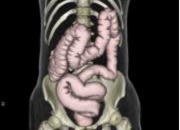

CTは2012年3月にAquilion ONE (320列CT)、 MRIは2014年2月に ECHELON OVAL (1.5T )が導入されました。320列CTは被ばく低減技術 AIDR3Dを使用することで通常のCT検査のみならず、CT検診も 大幅な被ばく低減 が可能となりました。大腸CT検診、肺がんCT検診では従来の1/5~1/10線量で検査をしています。

2012年4月には東北初となる、大腸CT検診もスタートしました。320列CTを使用し、ギリギリまで被ばく線量を下げた大腸CT検診、肺がんCT検診、心臓ドックを行っています。是非この機会に当院のCT検診をご利用ください。